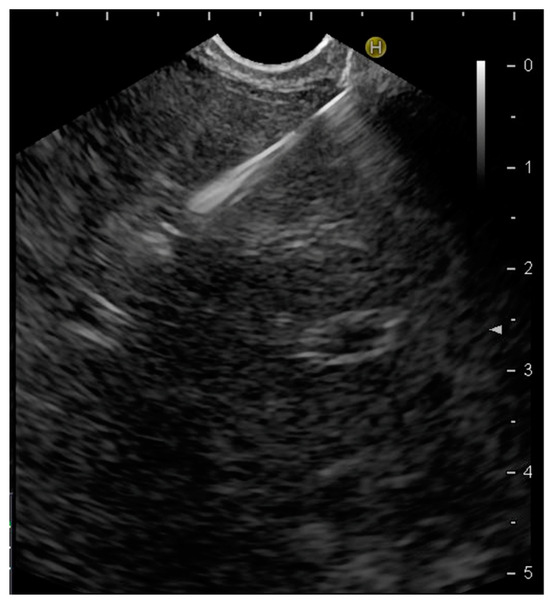

2.1. Patients and EUS-Guided Tissue Acquisition Method